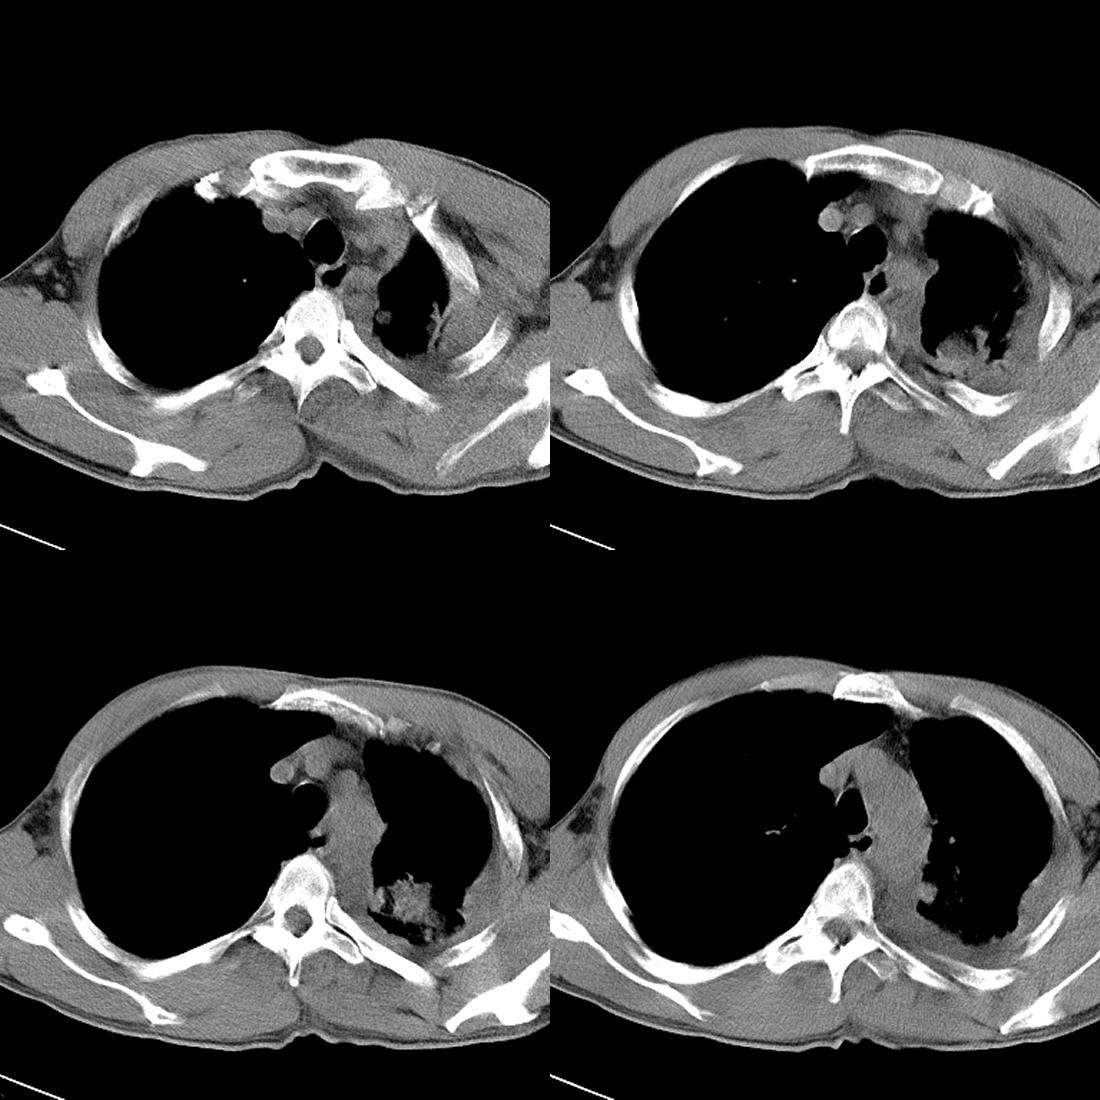

肋骨骨质破坏,考虑恶性。

左肺上叶周围型肺癌伴肺\\胸膜\\肋骨\\胸椎横突转移,左侧胸腔积液.

左侧椎体、横突、肋骨呈溶骨性破坏,半左侧胸腔中等量积液;左肺尖部可见一肿块影,边界欠清;多考虑恶性骨肿瘤,不除外肺尖部转移性表现可能。

左后部肋骨有破坏,应考虑肺癌并转移。。。。

左肺没见明显占位病变,但左肺门增大,不除外肿大淋巴结,左侧肋骨、胸椎融骨性破坏,考虑左侧胸膜恶性病变